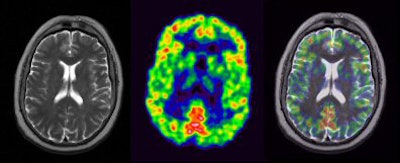

| FLAIR, ADC, T1 MPRAGE, and T2 TSE were applied during the same PET acquisition. PET shows absence of FDG signal from pathological periventricular regions. Images courtesy of Bernd Pichler, Ph.D., and colleagues at the University of Tübingen and David Townsend, Ph.D., and colleagues the University of Tennessee. |

| Comparative brain images with diffusion echoplanar imaging sequence applied during PET acquisition. Images courtesy of Bernd Pichler, Ph.D., and colleagues at the University of Tübingen and David Townsend, Ph.D., and colleagues at the University of Tennessee. |